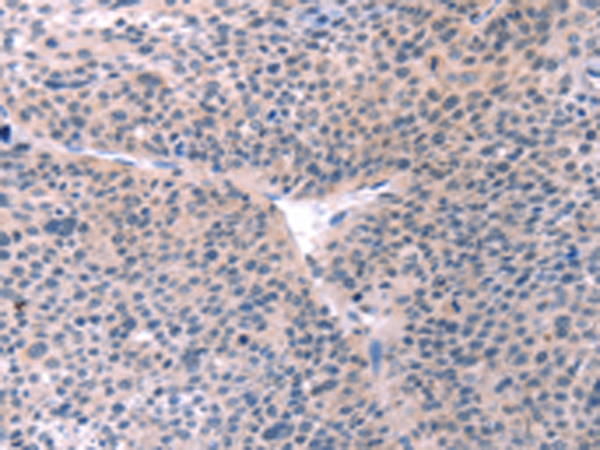

分类: 科研抗体货号: P07714别名: PSA; PROS; PS21; PS22; PS23; PS24; PS25; THPH5; THPH6应用: IHC反应种属: Human